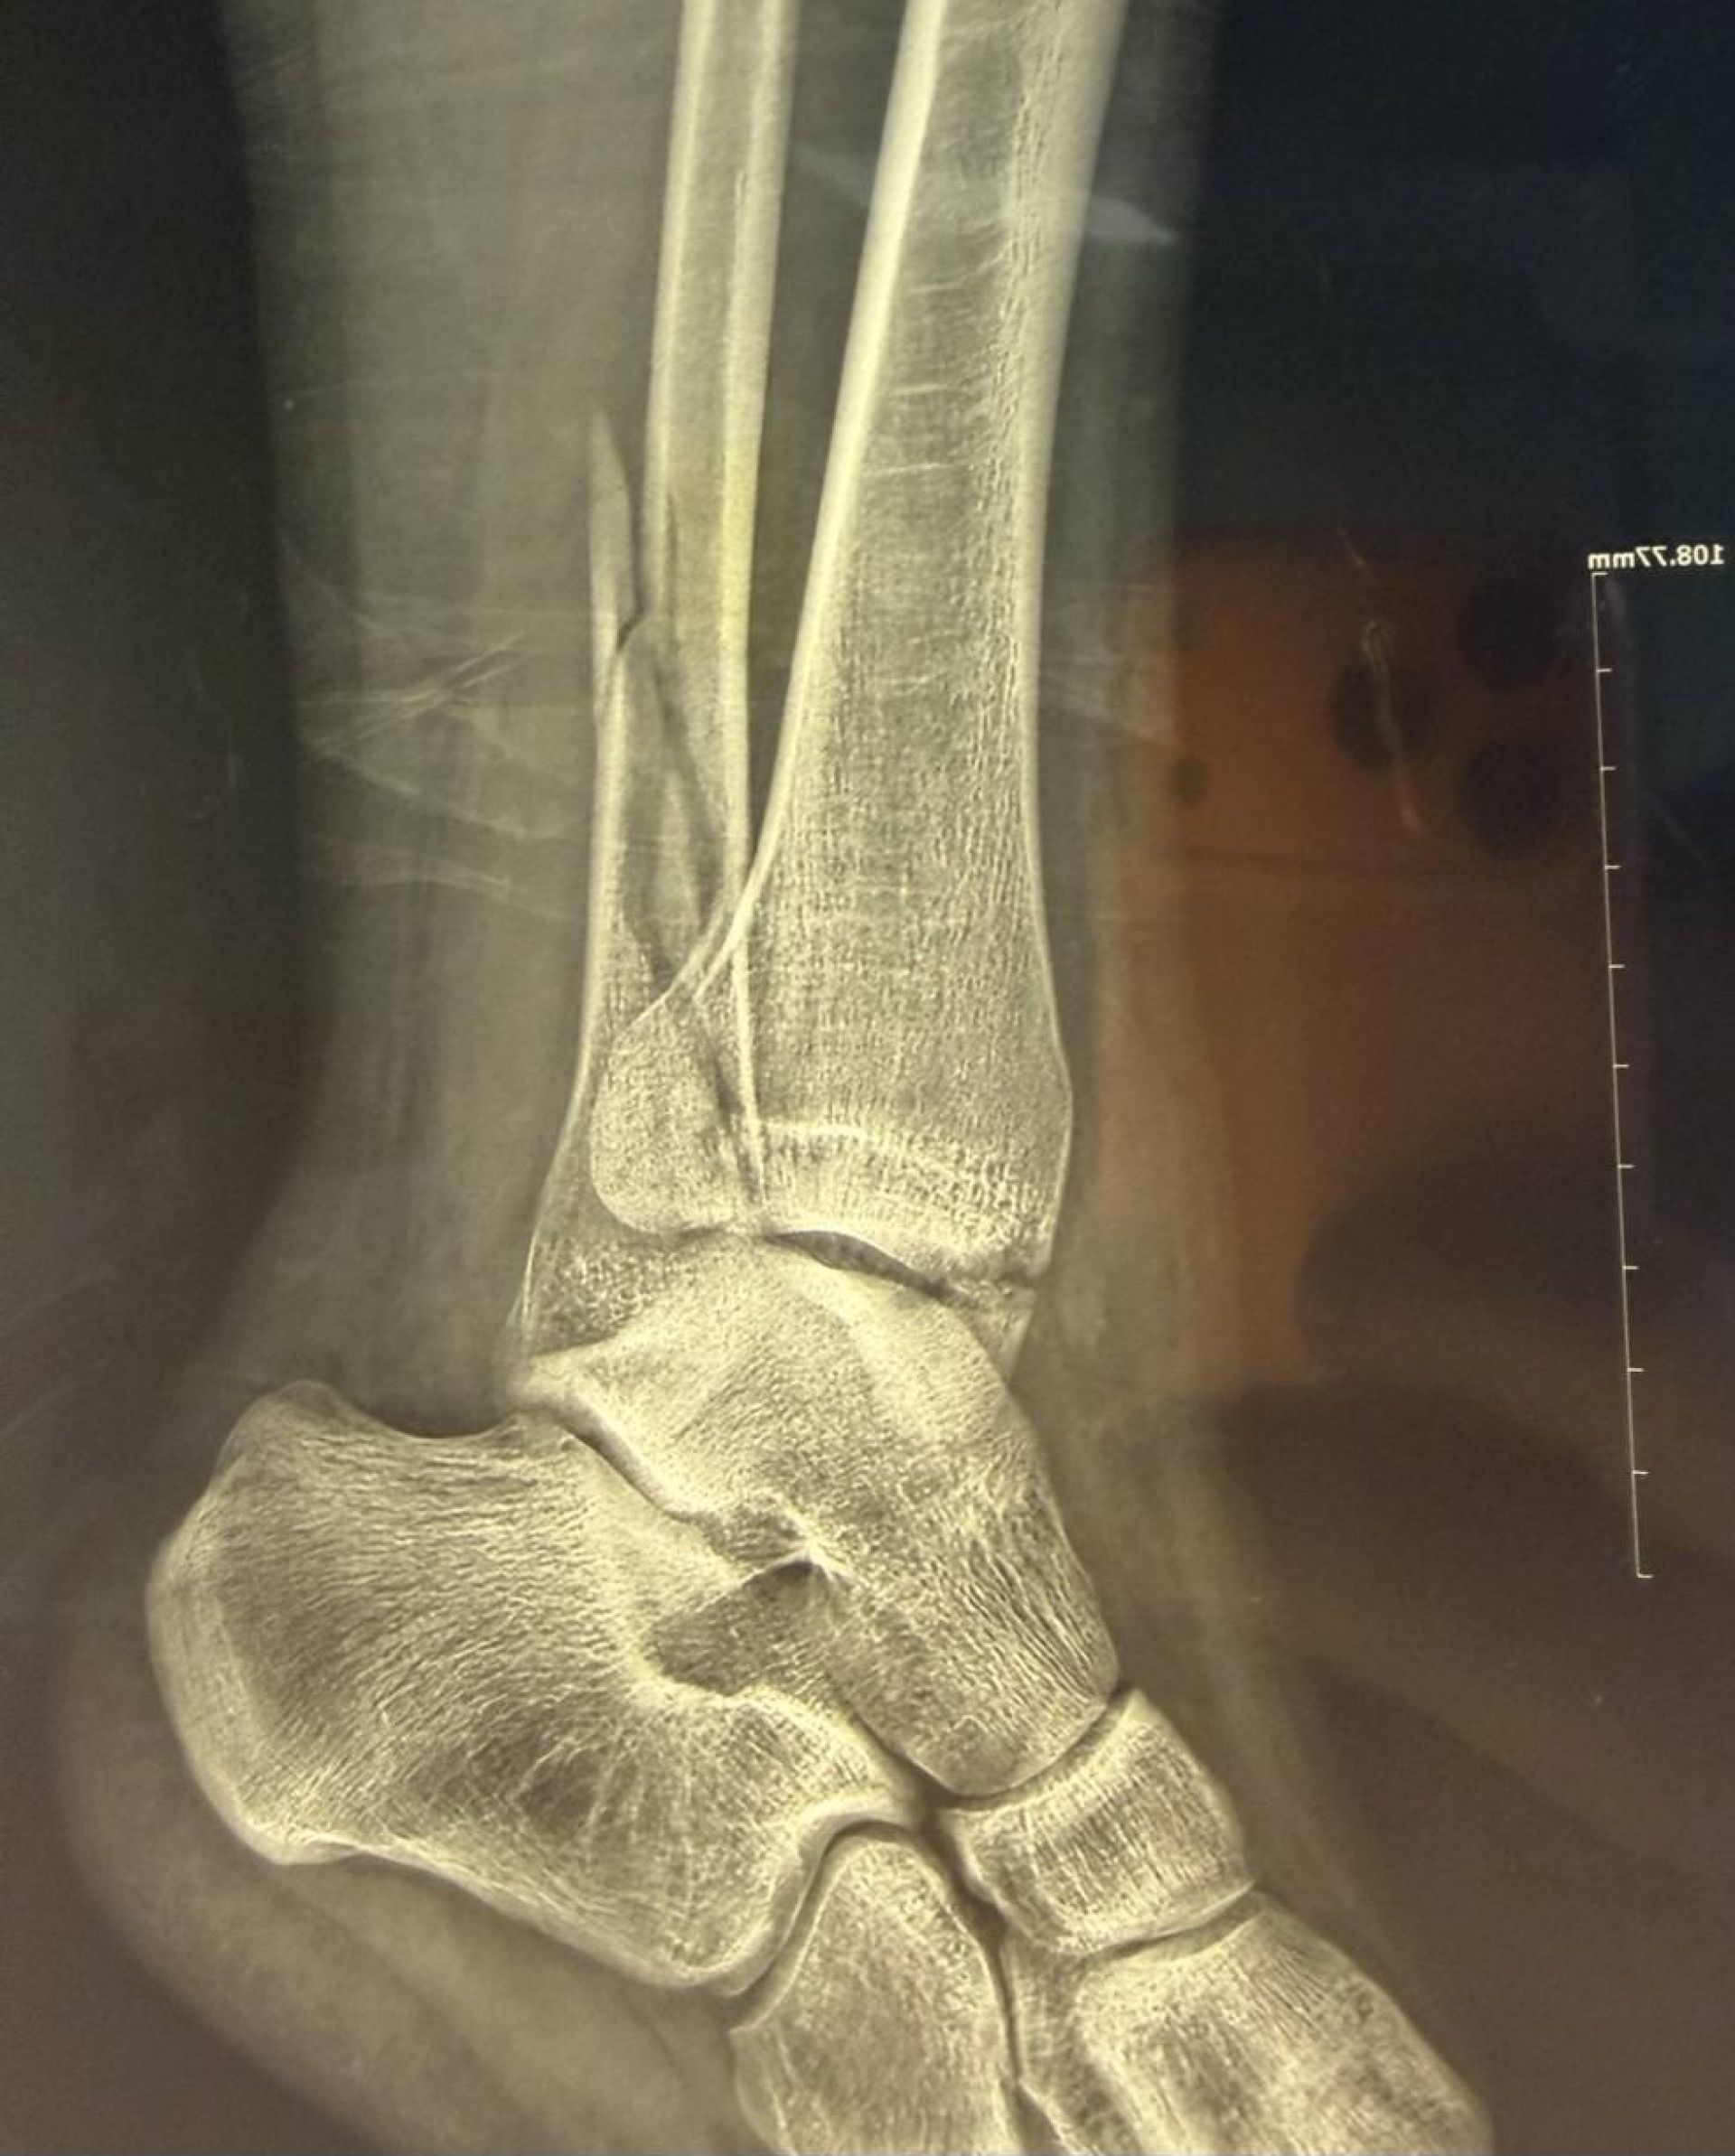

Хлопець звернувся до травмпункту, і обстеження показало, що він має не один, а цілих три складних переломи кісток гомілковостопного суглоба зі зміщенням.

Після госпіталізації та проведення додаткових обстежень (КТ) для максимально точного планування, фахівці лікарні провели складне оперативне втручання.

Головна мета операції полягала у тому, щоб зібрати всі кісткові уламки та повністю відновити стабільність суглоба. Хірурги виконали:

1. Зіставлення уламків малої гомілкової кістки та фіксацію її пластиною і гвинтами.

2. Репозицію переломів великої гомілкової кістки з фіксацією гвинтами.

3. Фіксацію суглоба спеціальним гвинтом для відновлення його стійкості.